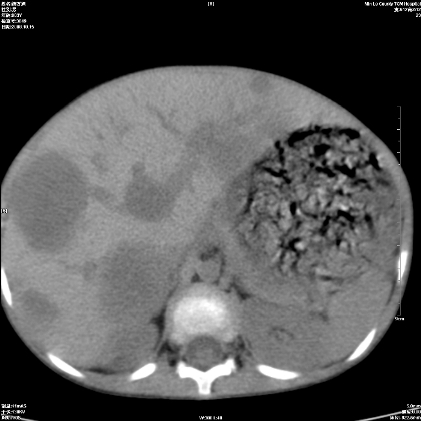

标题: PED1609:男性,3岁。彩超示肝Ca. [打印本页]

标题: PED1609:男性,3岁。彩超示肝Ca.

3岁;肝低密度灶;有钙化;有转移灶;考虑肝母细胞瘤;查afp

支持肝母细胞瘤肝内转移

考虑神经母细胞瘤并肝转移

考虑:1、右侧后下纵隔畸胎瘤。

2、肝脏多发血管内皮细胞瘤。

建议:增强确诊。